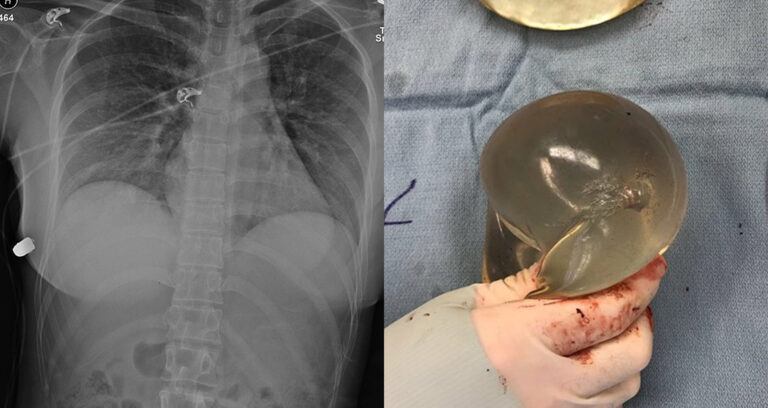

Canadian Woman’s Breast Implant Saved Her Life By Deflecting A Bullet

Doctors believe the bullet entered the woman's left side, was diverted by her implants, and then lodged behind her right breast where it remained until surgery.